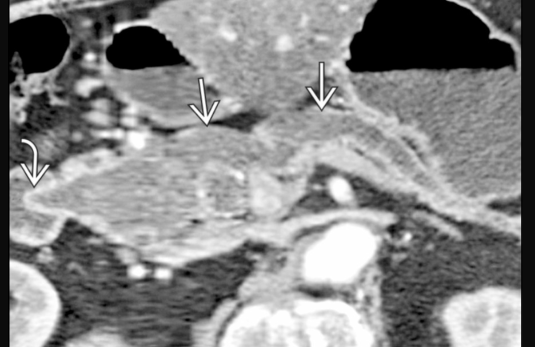

Dilatations du Wirsung et atrophie du pancres

TIPMP mixtes

TIPMP des petits canaux + wirsung a 6mm